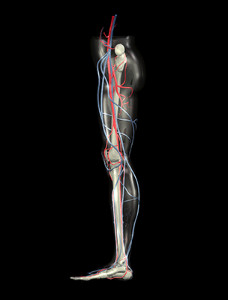

Read more about Blisters on the Feet If your feet feel cold, especially during these winter months, it is because it is your body’s natural response for conserving heat when it is too cold. Your body “tries to maintain its internal temperature by constricting small blood vessels under the surface of the skin. This allows more blood to move deeper in the body, so your core stays warm.” However, this causes your body’s extremities, like the feet, to receive poor blood circulation. When taking care of your cold feet, try to wear warm, breathable socks that help wick away moisture. Opt for wool in place of cotton. Other methods include warming your feet up in warm water, drinking hot liquids, moving around to get your blood circulation going, and investing in shoe inserts to help insulate the insides of your shoes.

If your feet feel cold, especially during these winter months, it is because it is your body’s natural response for conserving heat when it is too cold. Your body “tries to maintain its internal temperature by constricting small blood vessels under the surface of the skin. This allows more blood to move deeper in the body, so your core stays warm.” However, this causes your body’s extremities, like the feet, to receive poor blood circulation. When taking care of your cold feet, try to wear warm, breathable socks that help wick away moisture. Opt for wool in place of cotton. Other methods include warming your feet up in warm water, drinking hot liquids, moving around to get your blood circulation going, and investing in shoe inserts to help insulate the insides of your shoes.

Poor circulation is a serious condition and needs immediate medical attention. If you have any concerns with poor circulation in your feet contact Brent Harwood, DPM of Southeast Podiatry. Our doctor will treat your foot care needs.

Poor Circulation in the Feet

Poor blood circulation in the feet and legs is can be caused by peripheral artery disease (PAD), which is the result of a buildup of plaque in the arteries.

Plaque buildup or atherosclerosis results from excess calcium and cholesterol in the bloodstream. This can restrict the amount of blood which can flow through the arteries. Poor blood circulation in the feet and legs are sometimes caused by inflammation in the blood vessels, known as vasculitis.

Causes

Lack of oxygen and oxygen from poor blood circulation restricts muscle growth and development. It can also cause:

Those who have diabetes or smoke are at greatest risk for poor circulation, as are those who are over 50. If you have poor circulation in the feet and legs it may be caused by PAD and is important to make changes to your lifestyle in order to reduce risk of getting a heart attack or stroke. Exercise and maintaining a healthy lifestyle will dramatically improve conditions.

As always, see a podiatrist as he or she will assist in finding a regimen that suits you. A podiatrist can also prescribe you any needed medication.